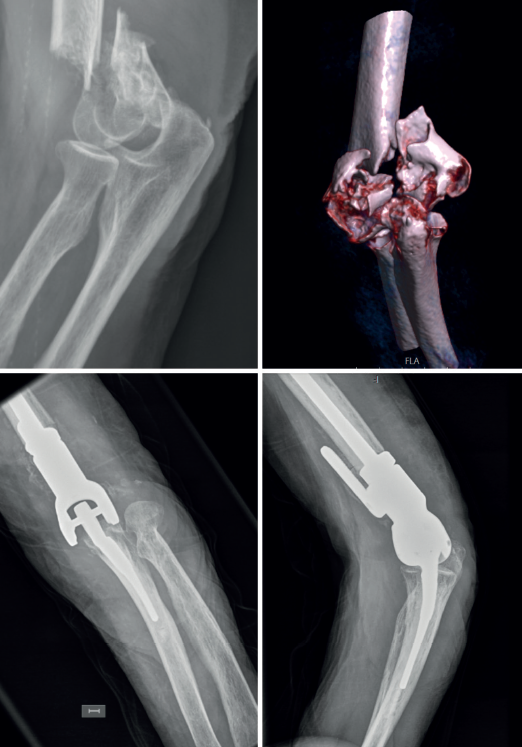

En consonancia con lo anterior, nosotros creemos que en la selección de la fractura que se va a intervenir con PTCodo es importante el uso de la tomografía computarizada para valorar y clasificar el tipo de fractura que tratar, porque si nos quedásemos con un estudio de radiología convencional difícilmente podríamos clasificar la fractura en el sistema AO (Figura 3). Todos los estudios incluidos para el tratamiento de fracturas de húmero distal mayoritariamente son fracturas de tipo C, pero en algunos casos A y B, por lo que nosotros adoptamos un protocolo propuesto por la Clínica Mayo para dicho tratamiento (Figura 2)(67), siendo muchas veces la decisión de emplear una PTCodo como tratamiento intraoperatoria. Mayoritariamente son fracturas cerradas, pero la existencia de fracturas abiertas no es una contraindicación, incluso se comunican fracturas de tipo IIIB de Gustilo(68).

En cuanto a la existencia de pseudoartrosis como en el caso de la Figura 4, hemos adoptado un algoritmo para ayudar en las decisiones de tratamiento relacionadas con las pseudoartrosis y las malas uniones del húmero distal (Figura 5). En este algoritmo hay preguntas clave que deben responderse antes de realizar una revisión con RAFI versus PTCodo y se relacionan con la superficie articular, la viabilidad de los fragmentos y la congruencia de la articulación. Si la restauración de la articulación es imposible, se emplea una PTCodo y los cirujanos deben sentirse cómodos tanto con la fijación como con el reemplazo. En general, como se ha comentado, el área supracondílea es la ubicación típica en la que se producen las malas uniones y las pseudoartrosis. Esto probablemente se deba al micromovimiento en los extremos de la fractura con poca área de contacto hueso con hueso y, en última instancia, a un fallo de la fijación. El área supracondílea debe comprimirse y mantenerse rígida para que cicatrice correctamente. La estrategia en las pseudoartrosis implica 4 principios clave: placas paralelas, acortamiento supracondíleo, autoinjerto de cresta ilíaca y liberación de la contractura. Los resultados después de este enfoque pueden lograr una alta tasa de unión con una función aceptable. De hecho, Donders et al. observaron la curación en 61/62 codos con esta estrategia, aunque el arco de movimiento se vio afectado con un arco promedio de 86(69). Ring et al. observaron la curación en 12 de 15 codos también, siendo la rigidez y los síntomas nerviosos las complicaciones más comunes(70). Como la rigidez es común dado el movimiento a través del sitio de la fractura en lugar de en la articulación, la liberación de la contractura es de suma importancia en el momento de la revisión. Además de un mejor movimiento, la liberación disminuye las fuerzas transmitidas al sitio de la fractura durante la curación.